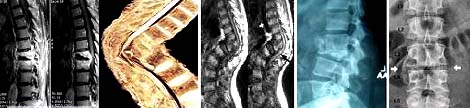

·Chụp Xquang có thể thấy hình ảnh tổn thương lao điển hình:

-Đĩa đệm hẹp lại và ở giai đoạn muộn các thận đốt sống dính sát lại với nhau, bờ thân đốt sống phía trên và dưới đĩa đệm bị phá hủy tạo hang lao, thân đốt sống bị xẹp, nhất là ở phía trước làm cho đốt sống có hình chêm và cột sống bị gù, mỏng gai của đốt sống đó lồi ra phía sau;

-Nếu có ổ áp-xe lạnh thì trên phim X-quang sẽ thấy bóng mờ của túi áp-xe lạnh;

-Hình ảnh X-quang của lao cột sống khác với tổn thương ung thư như sau: trong ung thư tổn thương chủ yếu ở đốt sống, đĩa đệm không bị tổn thương, vì vậy không thấy xẹp đĩa đệm và dính các đốt sống;

-Tổn thương do lao không có phản ứng dày xương, ngà xương kèm theo sự phá hủy xương. Tổn thương lao ít gặp ở cung sau đốt sống, vì vậy nếu thấy phá hủy ở cung sau có thể chẩn đoán do ung thư.